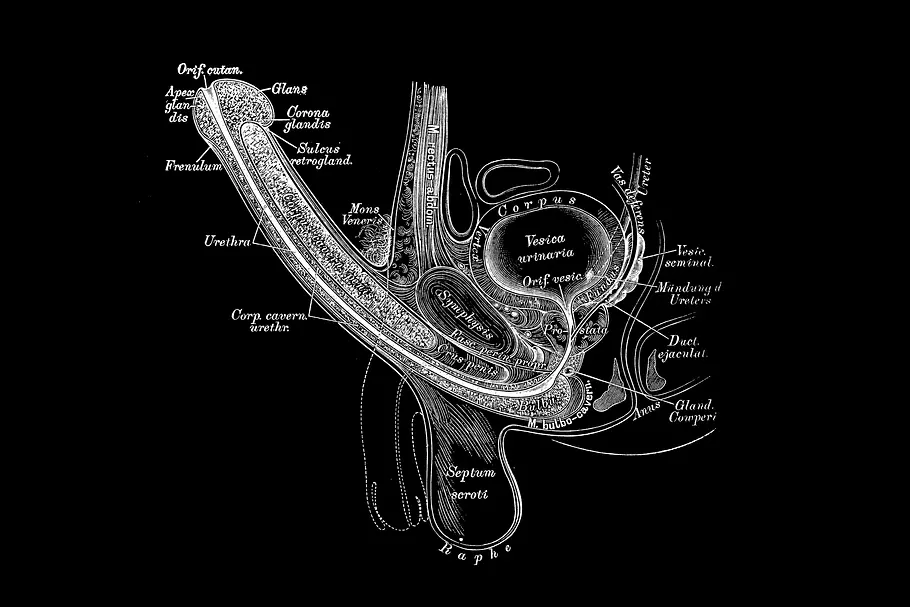

Der Penis des Mannes ist ohne Knochen. Aber der Penisknochen ist Realität - bei Hunden und anderen Säugetieren. Doch was ist das genau und wozu ist das sogenannte Baculum eigentlich gut?

Es gibt große Penisse, kleine Penisse und sogar ein Frenulum. Doch was der menschliche Penis nicht hat, das ist ein Knochen. Doch erstmal alles von Anfang:

Der menschliche Penis hat keinen Knochen, wie auch Prof. Dr. Frank Sommer & Oliver Bertram in "Das Men's Health Penis-Buch" erklären: "Er besteht aus verschiedenen Gewebearten und kommt bei Menschen im Gegensatz zu einigen (Säuge-)Tierarten ganz ohne knöcherne oder knorpelige Strukturen aus." (Sommer/Bertram: Das Men's Health Penis-Buch, S. 10)